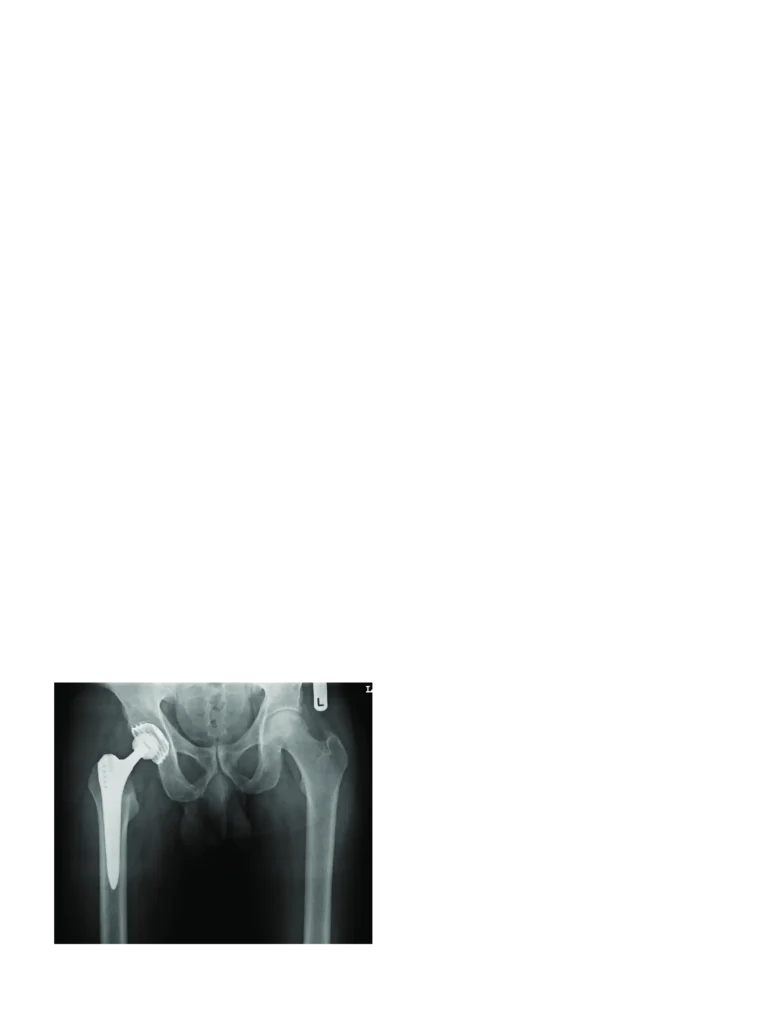

Hip pain can affect your ability to walk, bend, sit, sleep, or even perform routine movements without discomfort. At HappyKnees, we offer advanced Primary Hip Arthroplasty in Malad, performed by renowned orthopedic expert Dr. Akash Saraogi. This procedure—commonly known as Primary Hip Replacement—is designed to replace damaged hip joints with high-precision artificial implants, restoring smooth, pain-free movement.

Whether your hip damage is due to osteoarthritis, rheumatoid arthritis, osteonecrosis, congenital deformities, or trauma, primary hip arthroplasty provides long-lasting relief and improved mobility. With minimally invasive techniques, accurate implant positioning, and faster recovery protocols, HappyKnees ensures you return to a more active and independent life without long-term discomfort.

Primary hip arthroplasty is a surgical procedure in which the damaged parts of the hip joint are replaced with artificial implants. It helps relieve pain, restore mobility, and improve the quality of life for patients with severe hip joint damage.